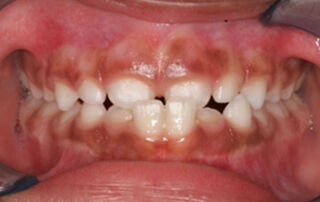

Caso clínico mordida cruzada anterior Brackets – 04

Niño en dentición mixta con Clase I que presenta una mordida cruzada anterior dental (MCAD). En las imágenes intraorales iniciales observamos la mordida cruzada anterior del incisivo central derecho superior con el incisivo central izquierdo inferior junto con una afectación gingival. En este caso se decidió colocar aparatología fija multibrackets [...]